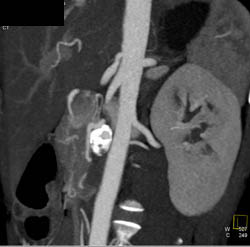

Partial Portal Vein Thrombosis (PVT) and Splenic and Superior Mesenteric Vein (SMV) Thrombosis